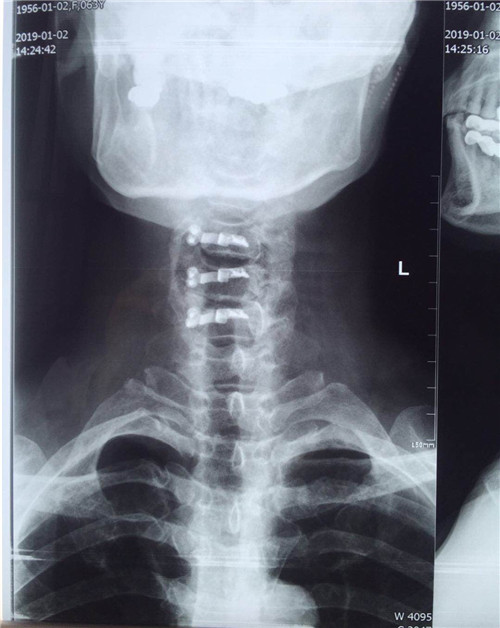

患者入院后,骨一科医护人员为其做进一步检查,诊断为多发颈椎间盘突出并继发颈椎管狭窄症。经讨论研究后,程福宏副主任医师决定为其行颈后路颈4、5、6的单开门椎板扩大成形术,该手术在王小峰主治医师的配合下完成。术中,医生为患者进行彻底的减压脊髓,固定椎板。术后患者恢复较好,症状改善明显,已能够独自行走,恢复正常活动。

术后